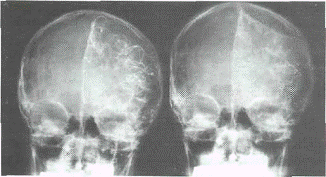

Ангиографический синдром ХСГ складывается

из характерной бессосудистой зоны между внутренней поверхностью костей свода

черепа и оттесненной корой мозга, а также дислокационных изменений в пробеге

магистральных сосудов соответственно топике ХСГ (при этом наиболее

демонстративны прямые ангиограммы, где бессосудистая зона имеет

линзообразную либо серповидную форму, особенно четко контурируясь в капиллярной

и венозной фазах - (рис.2).

Рис.2. Каротидная ангиграфия (прямая

проекция) - ХСГ лобно-теменно-височной области.